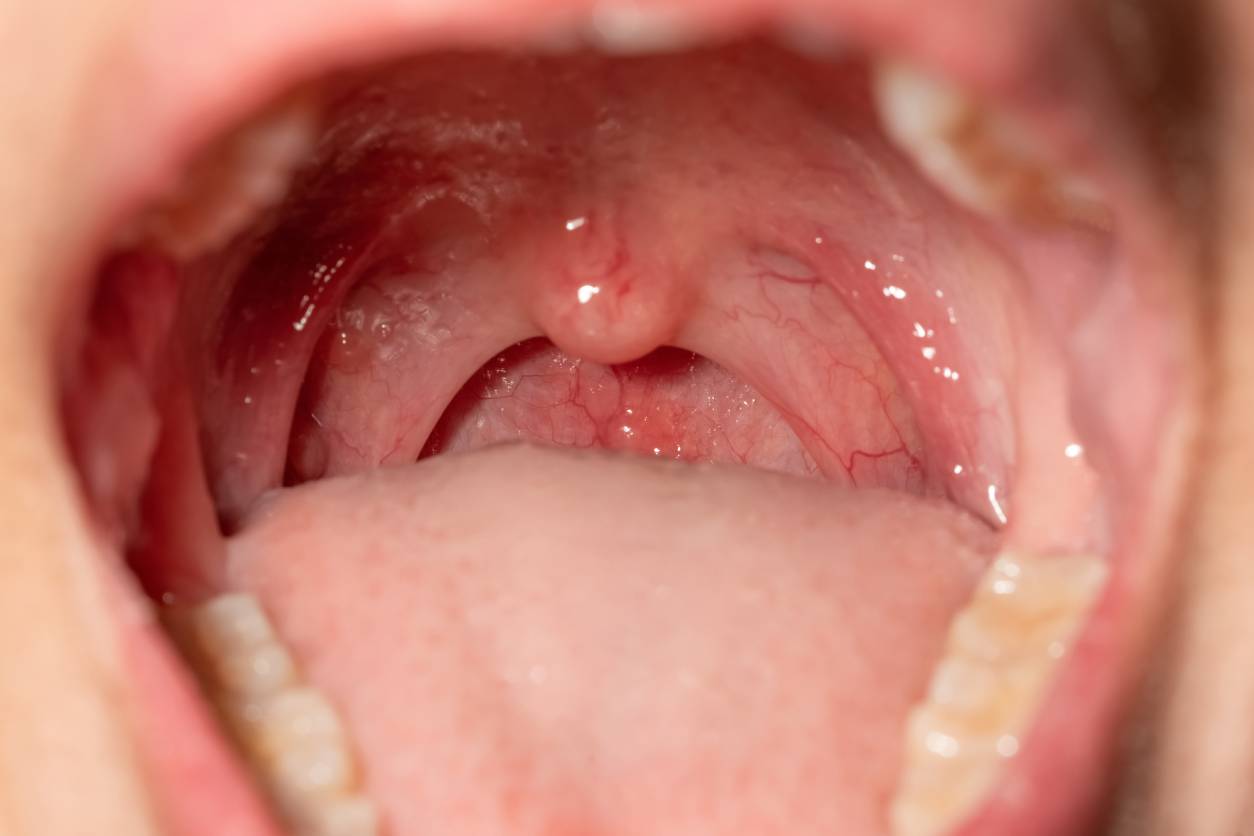

Tonsil conditions encompass a range of issues, including tonsillitis (infections), tonsil stones (calcified debris), or enlarged tonsils, often triggered by bacteria, viruses, or trapped material, resulting in persistent sore throats, bad breath, or disrupted sleep. Dr. Naveed Basheeth employs advanced diagnostic techniques, such as detailed throat examinations and high-resolution imaging, to thoroughly assess tonsil issues, delivering customized treatments that swiftly alleviate symptoms and restore throat comfort for lasting relief.

Tonsil treatment uniquely targets disorders like tonsillitis, tonsil stones, or tonsil enlargement, distinguishing it from ENT specialties addressing ear, nasal, or sinus conditions. It integrates precise diagnostic tools, including throat swabs and endoscopic visualization, with tailored interventions such as antibiotics, manual tonsil stone removal, or tonsillectomy. This focused approach ensures rapid symptom relief, restores throat function, and enhances overall comfort with minimal invasiveness.